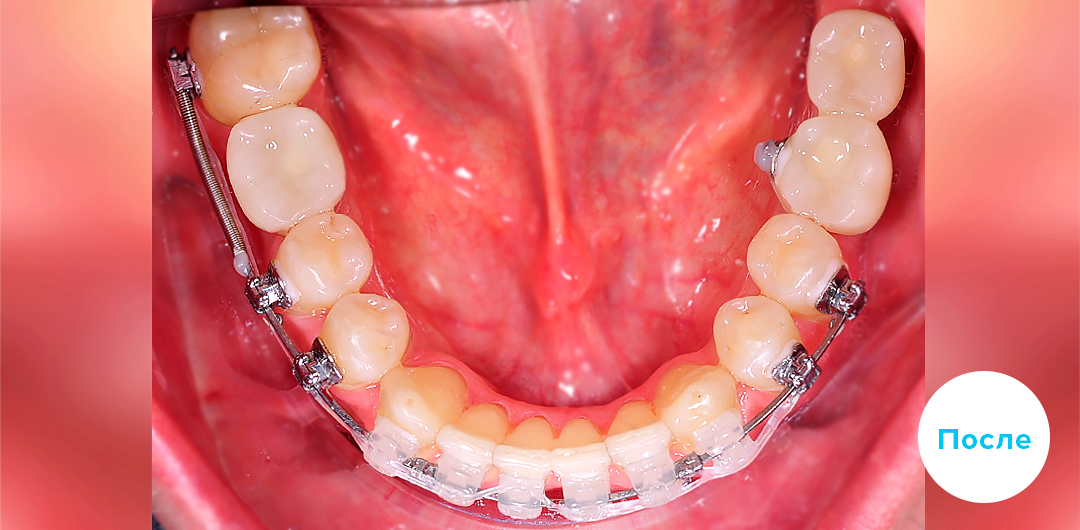

Результаты лечения